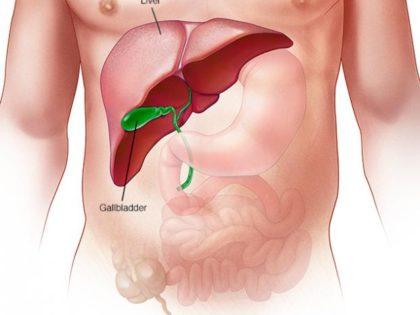

Pregnant women are advised to sleep on their left, especially in the third trimester, as this position allows for optimal circulation of blood and oxygen for mother and child. A growing fetus puts a lot of pressure on a woman’s internal organs like the liver and spine. Lying on the left side ensures that this is kept at a minimum and that there is good blood flow for both bodies.